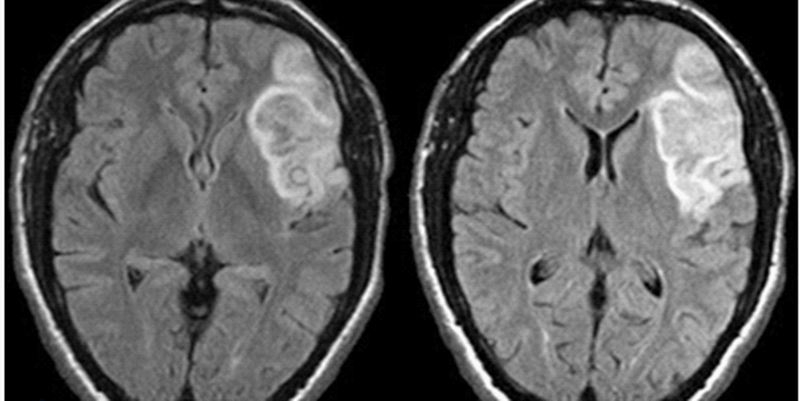

1. Metformin was found to be safe and tolerable in survivors of pediatric brain tumors.

2. Metformin was associated with retention of memory and processing speed abilities, as well as a reduction of white matter loss.

It is believed that endogenous neural precursor cells (NPCs) can promote tissue repair in the human brain due to its precursor cell populations. This is an important consideration due to limited self-repair capacities of the brain, such that agents inducing proliferation and differentiation of NPCs in vivo, validated in rodent models, could benefit humans. The hypoglycemic agent metformin has been found to increase neurogenesis in rodent models, particularly through activating the atypical protein kinase C (APKC)-CREB-binding protein (CBPT) pathway in NPCs. Metformin also improved cognitive faculties such as spatial memory. Its ability to decrease disease-related hippocampal neuron loss, metformin may also have the ability to recruit NPCs to repair brain tissue in humans. This pilot randomized, double-blind, placebo-controlled clinical trial with crossover focused on survivors of pediatric brain tumors treated with cranial radiation due to the hippocampus and white matter, high in NPCs, are most commonly damaged during cranial radiation. Specifically, safety and feasibility of metformin among this population was investigated. A total of 24 participants were randomly assigned to 12-week cycles of metformin (n = 11; M [SD] age = 7.26 [3.34] years) and placebo (n = 12; M [SD] age = 6.44 [3.63] years) in either an AB or BA sequence. A 10-week washout period occurred at crossover. Cranial radiation of participants occurred 2 to 15 years prior to the study. Blood draws, MRI, medication and procedural adherence, and cognition were measured throughout the study. A total of 12 participants were medulloblastoma survivors. This study found that, in spite of increased mild gastrointestinal events, metformin was both tolerable and safe. It also appeared that metformin reduced the negative impacts of radiation on processing speed, memory, and white matter loss consistent with the population. While this study’s sample was relatively small, it suggests that metformin may be beneficial to this population through the recruitment of NPCs to repair tissue damage and retain cognitive faculties.